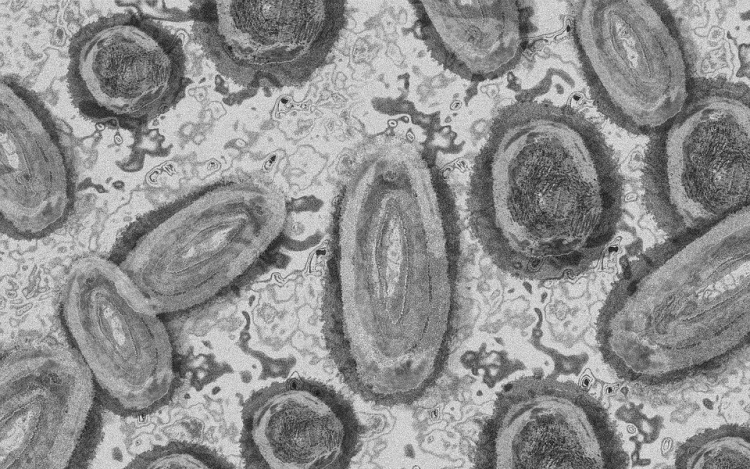

Meghaladta a 13 ezret a majomhimlő-fertőzöttek száma az Egyesült Államokban, a legtöbb esetet Kaliforniában és New York államban regisztrálták.

Az amerikai járványügyi és betegségmegelőzési központ (CDC) szerdán közölt friss tanulmánya szerint a járvány ugyan elsősorban szexuális érintkezés útján terjed, de a fertőzöttek egy része tömegrendezvényeken kapta meg a vírust. A hivatal arra hívja fel a figyelmet, hogy a majomhimlővel bárki megfertőződhet, ha másokkal közeli testi kapcsolatba kerül, akár bőrfelületek érintkezése révén.

A legutóbbi adatok szerint 13 500 fölött van az igazolt fertőzöttek száma, az esetek csaknem felét Kalifornia, New York és Florida államokban regisztrálták.